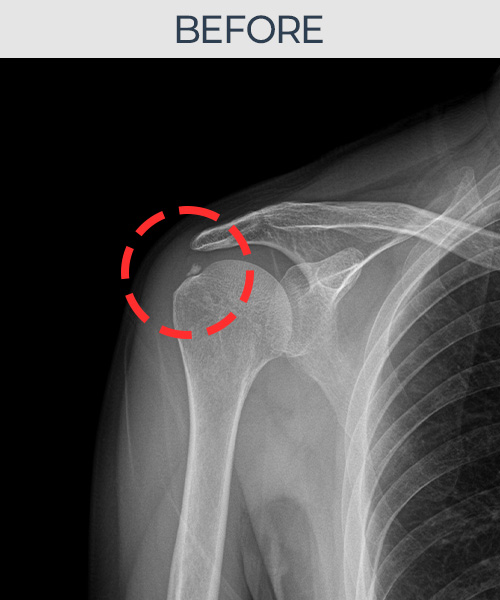

수천건의 수술 경험을 바탕으로 정확히 진단하여

인대파열을 비수술로 치료합니다.

플래티넘정형외과에서는 수술이 필요없는 인대파열만을

정확히 진단하여 특허받은 술기로 비수술로 치료합니다.